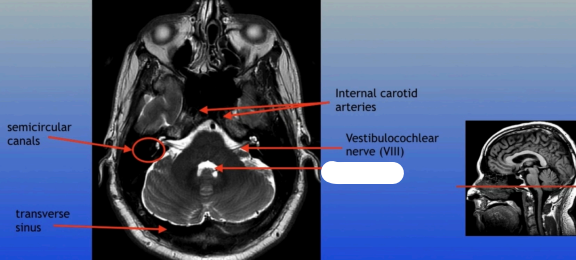

Semicircular Canals

Transverse Sinus

Internal Carotid Arteries

Vestibulocochlear Nerve (VIII)

4th Ventricle